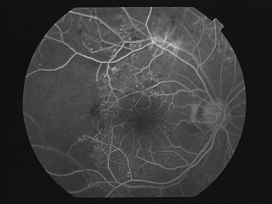

網膜の血管の異常を把握するために、造影剤を静脈注射した後、約15分間眼底写真を撮影する検査です。検査中は青く強い光量で撮影するため、まぶしさを感じます。血管の状態や虚血部位が確認できるので、治療法を決定するために行います。